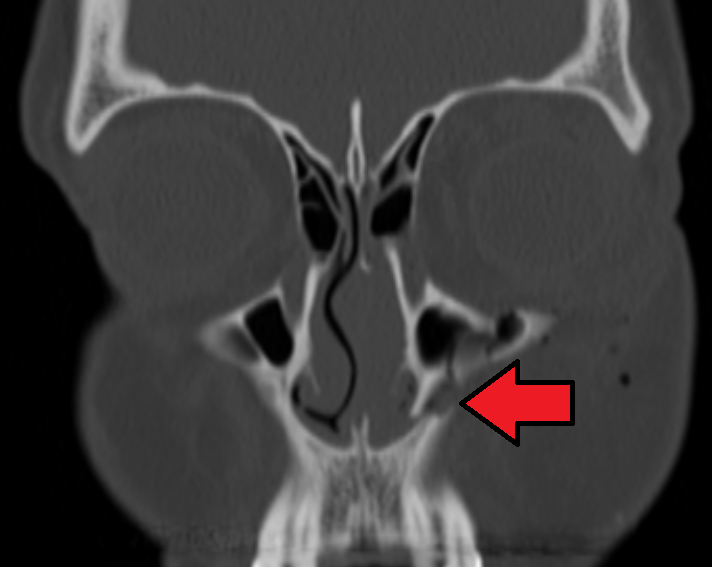

Fracture du maxillaire superieur

Demander un scanner.